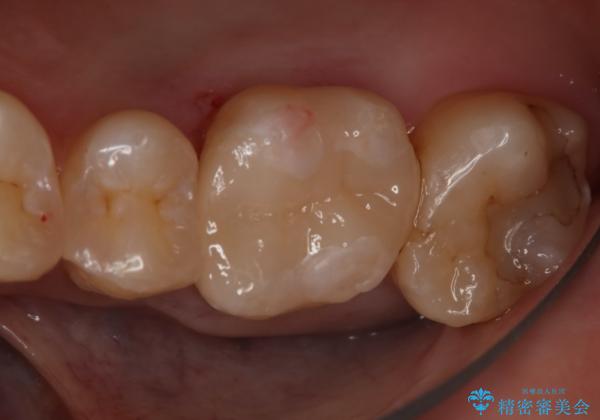

- 右上6番の銀歯をセラミックに変えたいと希望された患者様です。

切削量、形態を考慮し、セラミックインレーでの治療を計画しました。

銀歯と虫歯を除去した上でCRで裏層し形態を整えて印象を行っています。